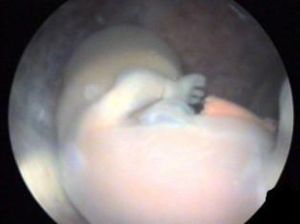

對肝、腎功能不良,患嚴重全身性疾患者,如心衰、重度貧血或各種疾病急性期患者,以及生殖器官管,順宮壁四周輕輕刮淨或吸淨殘留組織,保留所有鉗吸出的孕產物,以確定流產完全(見圖)。